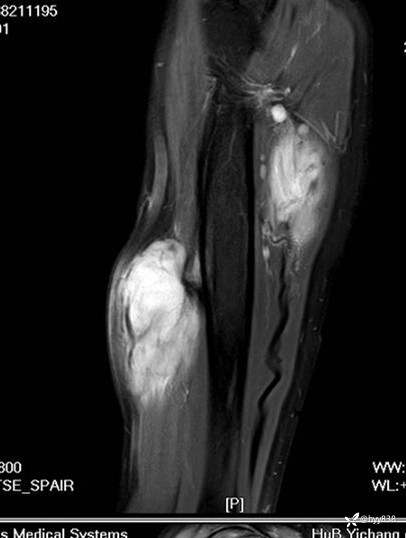

SAG T1WI+PDWI fs